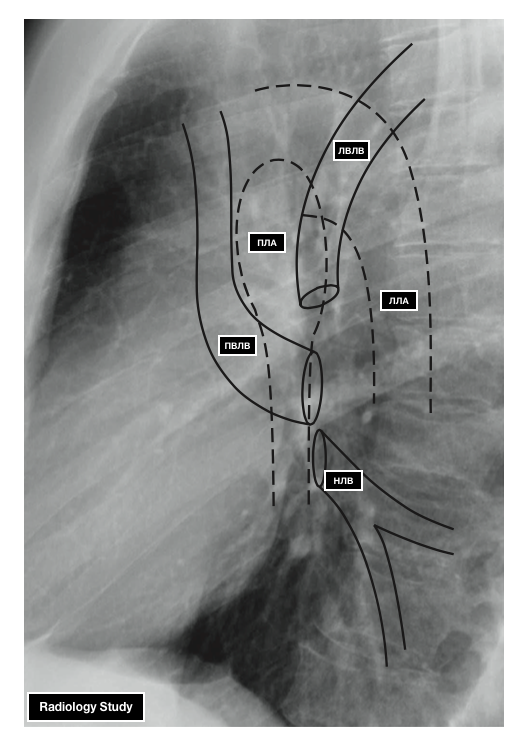

- ЛВЛВ — левая верхняя легочная вена

- ПВЛВ — правая верхняя легочная вена

- НЛВ — нижняя легочная вена

- ПЛА — правая легочная артерия

- ЛЛА — левая легочная артерия

Боковая проекция. Легочный ствол расположен по продолжению артериального конуса правого желудочка и проекционно совпадает с восходящей аортой. При контрастировании дифференцируется книзу и кпереди от раздвоения трахеи.

Правая легочная артерия дает интенсивную округлой или овальной формы тень в корне правого легкого, отчетливо определяемую лишь при контрастировании. При бесконтрастном исследовании контуры ее видны нечетко из-за проецирующихся сегментарных сосудов.

Левая легочная артерия образует дугообразную тень, огибающую округлое просветление поперечного сечения левого главного и верхнего долевого бронхов, нижний ствол ее отклоняется кзади.

Рис. 213. Ангиограммы легких в прямой и левой боковой проекциях. Контрастирова-ны правый желудочек и разветвления легочной артерии.Магистральный тип ветвления сосудов легких.

7 — правый желудочек; 2 — артериальный конус; 3 — легочный ствол; 4 — правая легочная артерия; 5 — левая легочная артерия; 6 — правая верхняя долевая артерия; 7 — левая верхняя долевая артерия; 8 — правая нижняя долевая артерия (нижний ствол); 9 — левая нижняя долевая артерия

(нижний ствол).